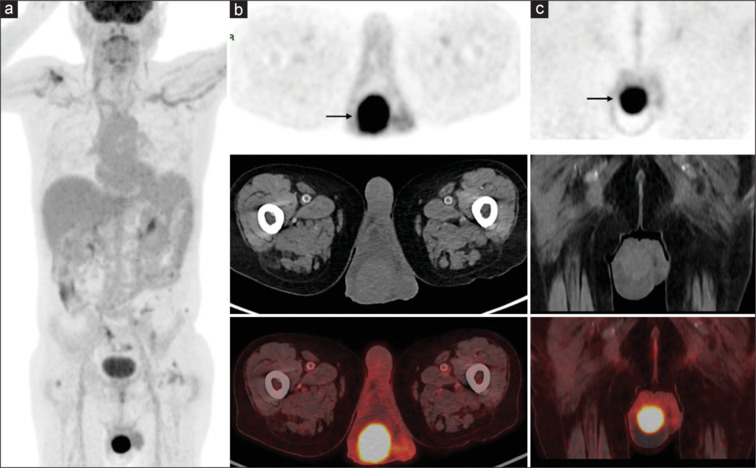

False positive findings in 18F-fluorodeoxyglucose positron emission tomography-computed tomography (18F-FDG PET/CT) scans can present challenges in the accurate diagnosis and staging of various conditions. We report a case of a 52-year-old male with known adenocarcinoma of the stomach who underwent total gastrectomy and chemotherapy and was referred for 18F-FDG PET/CT to rule out recurrence. 18F-FDG PET/CT showed a large FDG-avid lesion involving the entire right testicle mimicking testicular cancer or lymphoma. Further evaluation with ultrasonography revealed epididymo-orchitis, possibly of granulomatous etiology. Orchitis, an inflammatory condition of the testicles, can cause misleading results in 18F-FDG PET/CT imaging for cancer surveillance. Imagers should cautiously interpret PET/CT findings, considering clinical context, patient history, and additional imaging modalities to distinguish true malignancies from false positives.